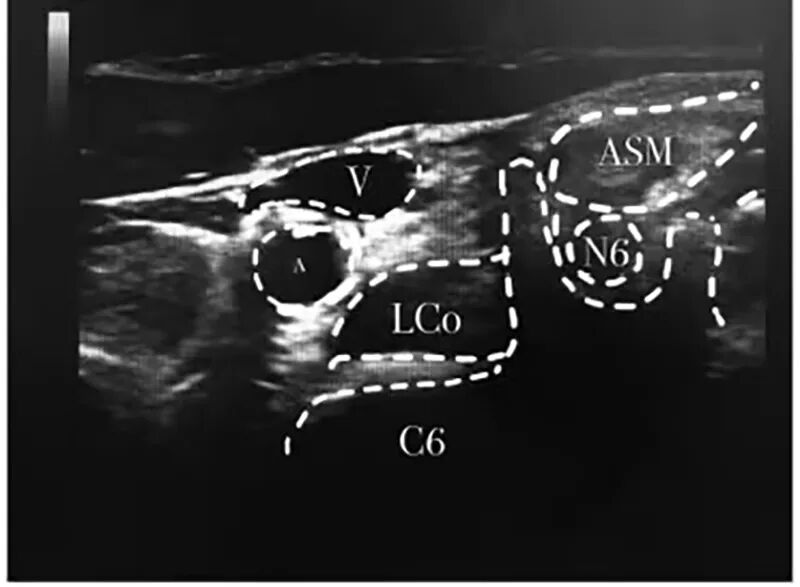

由于患者已尝试了一般疗法、药物治疗和经穴治疗,均未能阻止其打嗝,并持续7日,最后在医师的推荐下,由麻醉科为其进行“超声引导下膈神经+星状神经节阻滞”治疗。

麻醉科童主任说:膈神经阻滞治疗顽固性呃逆主要是通过阻断呃逆的反射弧,减低膈神经应激性,达到终止呃逆的目的。星状神经节阻滞治疗顽固性呃逆其机制是通过药物扩散,阻断颈胸交感神经节前和节后纤维,抑制交感神经支配的组织器官的交感活动效应,干扰膈神经冲动,同时亦能调理下丘脑和植物神经功能,改善由于植物神经功能紊乱引起的膈肌痉挛状态。能起到立竿见影的作用。